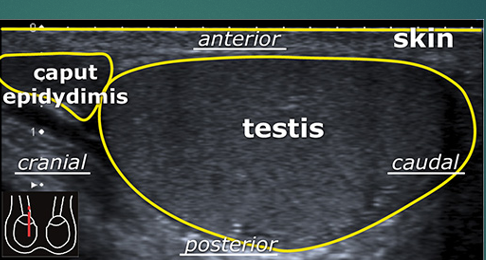

List caudal, cranial, anterior and posterior

list the 2 pieces of anatomy

what do you see